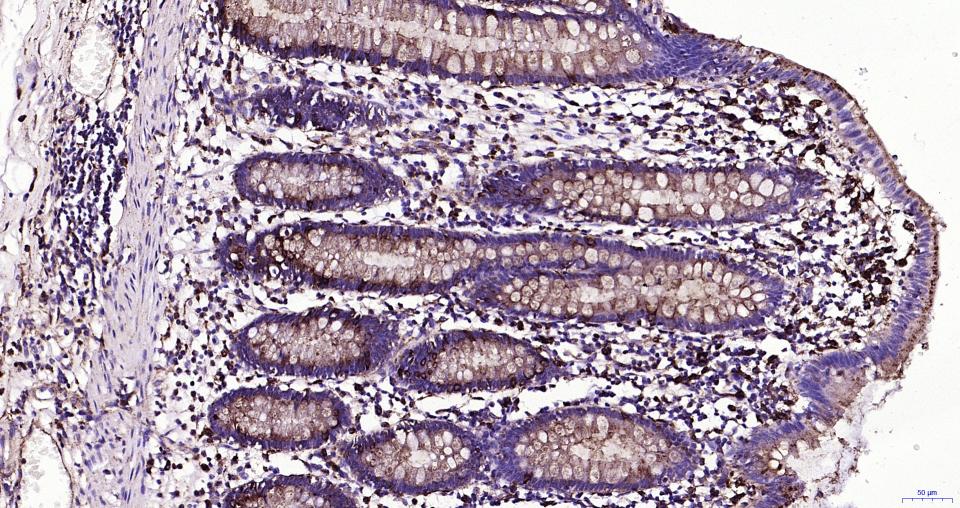

Paraformaldehyde-fixed, paraffin embedded Human Small Intestine; Antigen retrieval by boiling in sodium citrate buffer (pH6.0) for 15 min; Antibody incubation with LAMP1 Monoclonal Antibody, Unconjugated(bsm-61375R) at 1:200 overnight at 4°C, followed by conjugation to the SP Kit (Rabbit, SP-0023)and DAB (C-0010) staining.